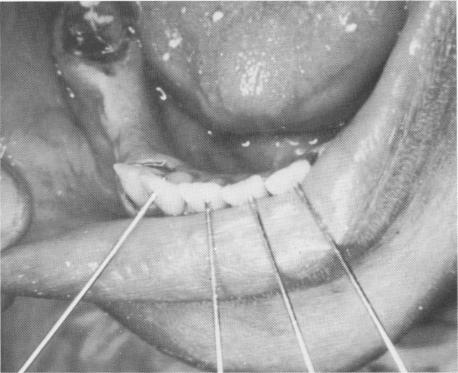

Fig. 11-85. Nonparallel pins inserted labially above the pulp horns.

1 Nonparallel pins inserted labially above mandibular teeth pulp horns